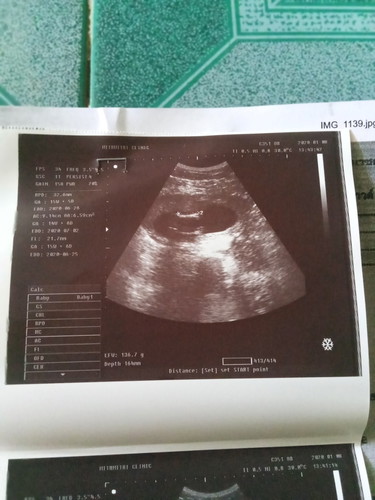

แล้วรูปนี้ละค่ะ..ดูไม่เข้าใจเลย😄 คุณหมอก็ไม่บอกอะไรเลยค่ะ

กระดูกสันหลังจ้า ซาวด์ครั้งที่ 2 บ้านนี้ก็ได้ภาพนี้คะ